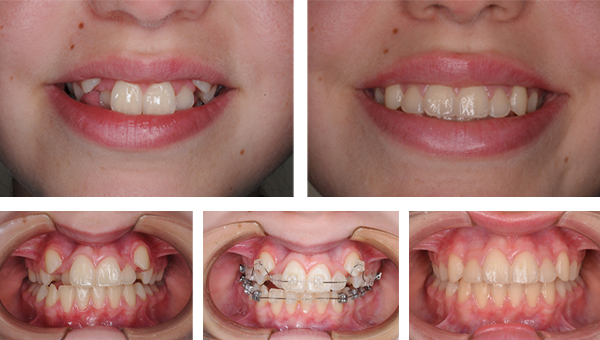

En el caso de que el ortodoncista detecte un trastorno en la mordida, en la salida de los dientes, en la respiración o un hábito que esté impidiendo el correcto desarrollo de la boca (chupeteo de dedo, deglución infantil), habrá que realizar un estudio de ortodoncia y planificar una 1ª fase de tratamiento para resolver el problema. Una vez que hayan salido los dientes definitivos, se realiza un nuevo estudio y, en el caso necesario, se planifica una 2ª fase de ortodoncia para dar la estética final y mordida adecuadas a cada caso.